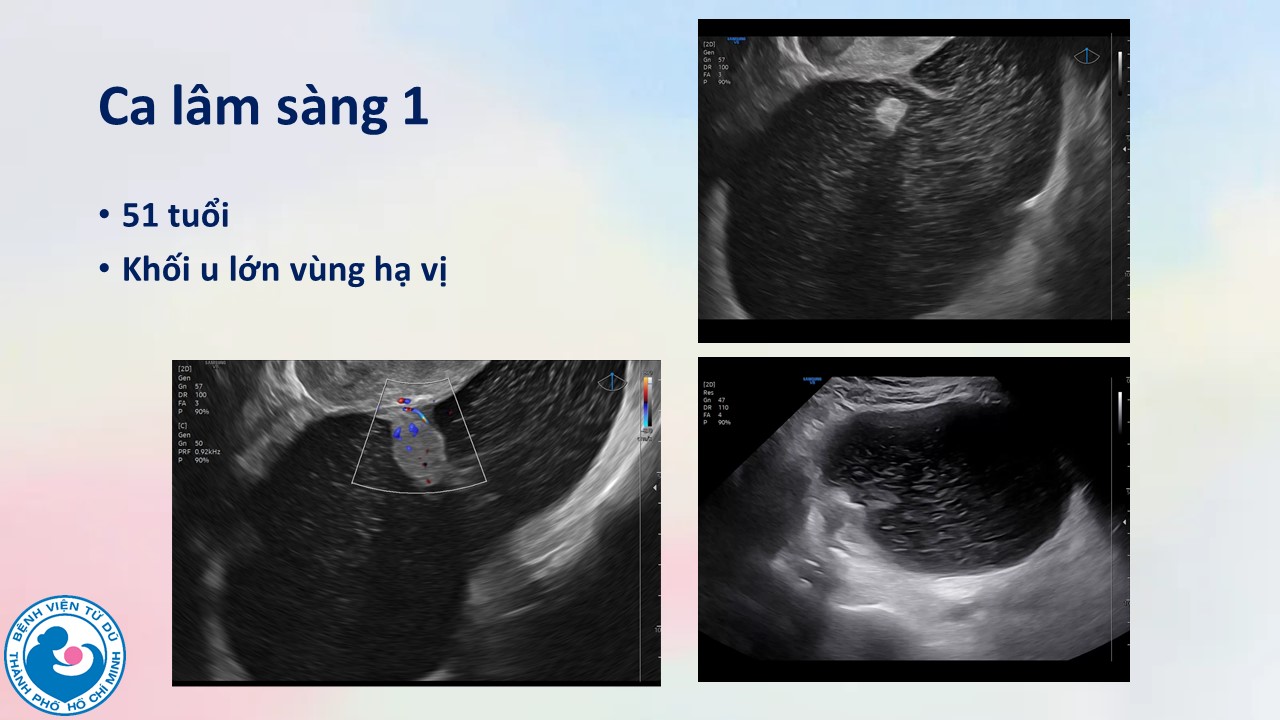

Ứng dụng mô hình ADNEX để chẩn đoán ung thư bường trứng trước phẫu thuật: kinh nghiệm tại bệnh viện Từ Dũ

BS. CKI Vũ Quốc Hùng, Ths. BS. Hà Tố Nguyên - Bệnh viện Từ Dũ